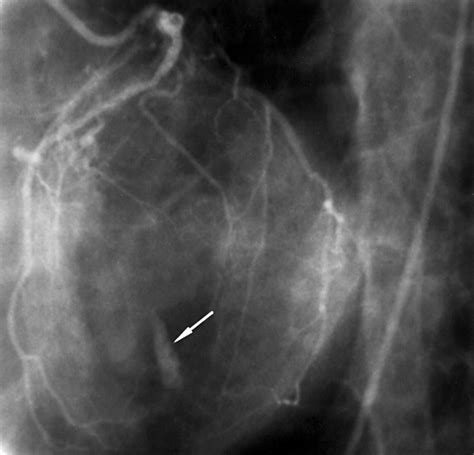

• Coronary Angiography: A procedure that uses dye and X-rays to visualize the coronary arteries and identify blockages.